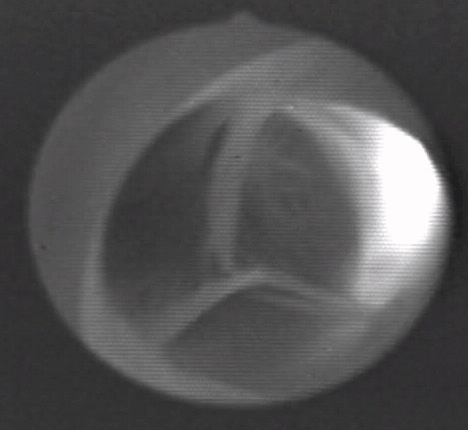

- пик открытия створок, приходится на первую фазу максимального изгнания крови: свободные края створок максимально изгибались в сторону синусов, форма открытия клапана приближается к кругу;

- период устойчивого открытия створок, приходится на вторую фазу максимального изгнания крови: свободные края створок выпрямляются вдоль оси потока, клапан принимает форму цилиндра, и створки постепенно прикрываются, форма открытия клапана становится треугольной;